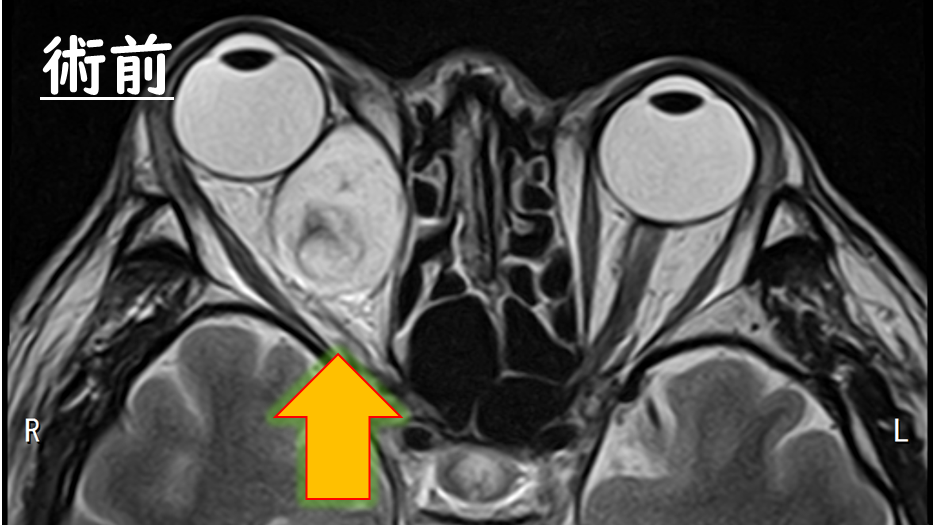

術前のMRI

眼球より後方に腫瘍があり、眼球を押し上げていることが分かります。

術後MRI

腫瘍はきれいに摘出され、眼球は凹んでいます。